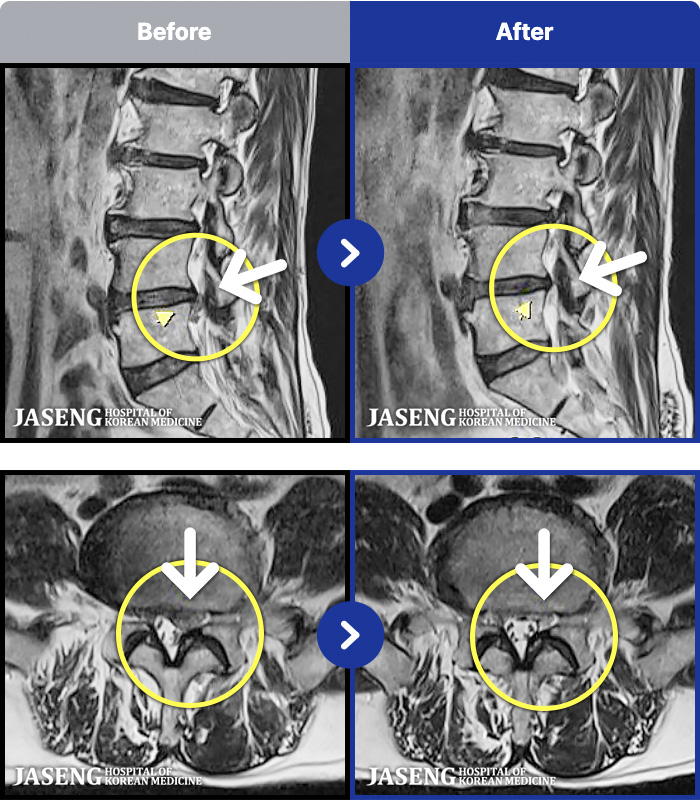

1,299 MRI ũ ʸ Ȯϼ.